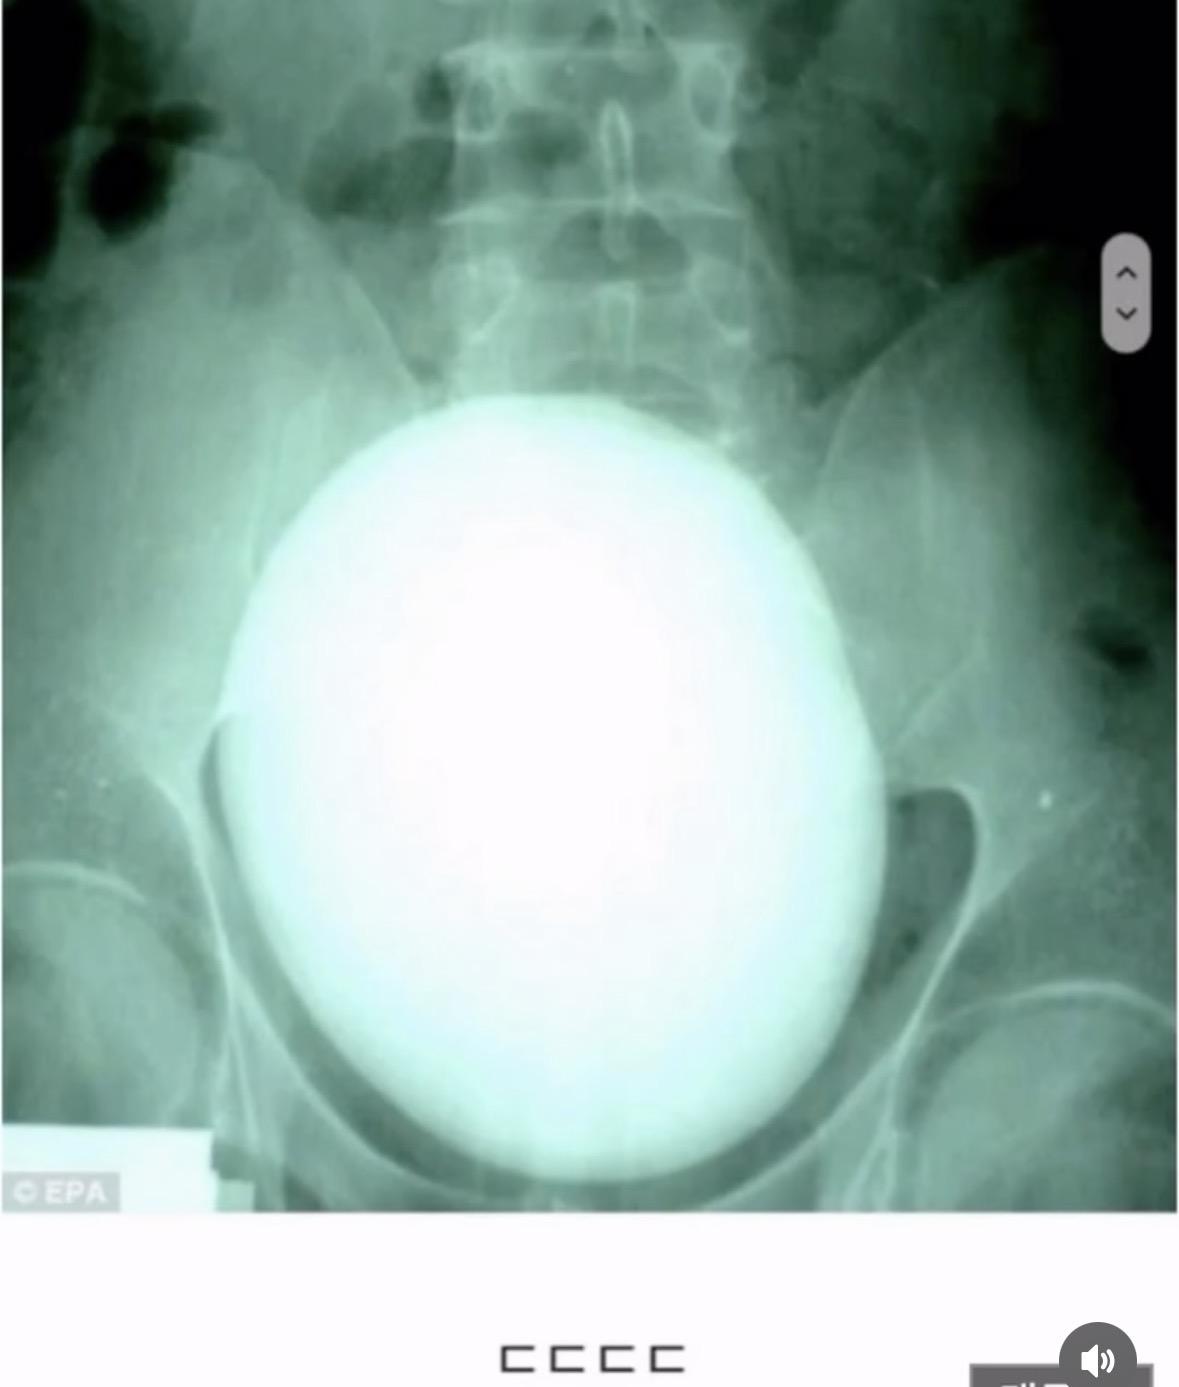

남자도 알을 낳을 수 있다..